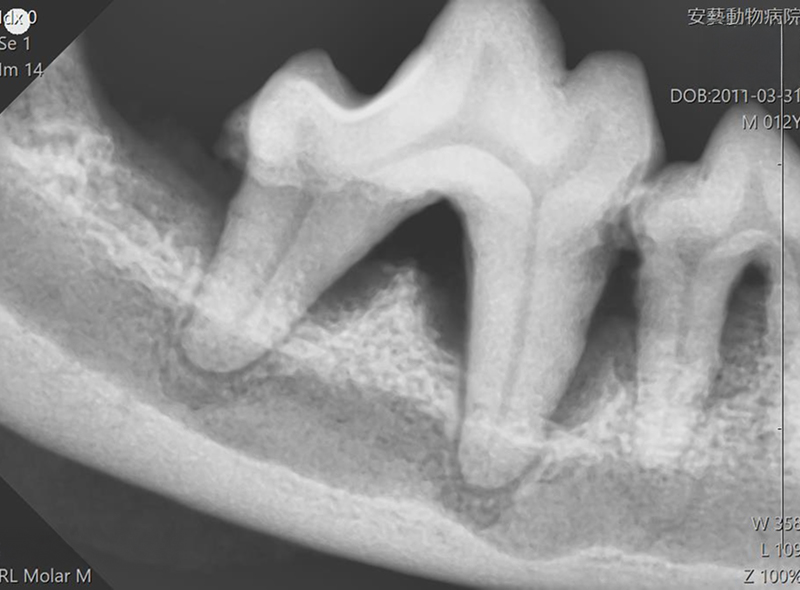

下記の画像は、初回治療時の歯科X線画像と3ヶ月後の歯科X線画像です。歯槽骨の回復が認められます。

初回治療後

3か月後